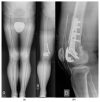

Osteoarthritis is a degenerative condition affecting the whole joint with the underlying bone, representing a major source of pain, disability, and socioeconomic cost worldwide. Age is considered the strongest risk factor, albeit abnormal biomechanics, morphology, congenital abnormality, deformity, malalignment, limb-length discrepancy, lifestyle, and injury may further increase the risk of the development and progression of osteoarthritis as well. Pain and loss of function are the main clinical features that lead to treatment. Although early manifestations of osteoarthritis are amenable to lifestyle modification, adequate pain management, and physical therapy, disease advancement frequently requires surgical treatment. The symptomatic progression of osteoarthritis with radiographical confirmation can be addressed either with arthroscopic interventions, (joint) preservation techniques, or bone fusion procedures, whereas (joint) replacement is preferentially reserved for severe and end-stage disease. The surgical treatment aims at alleviating pain and disability while restoring native biomechanics. Miscellaneous surgical techniques for addressing osteoarthritis exist. Advanced computer-integrated surgical concepts allow for patient personalization and optimization of surgical treatment. The scope of this article is to present an overview of the fundamentals of conventional surgical treatment options for osteoarthritis of the human skeleton, with emphasis on arthroscopy, preservation, arthrodesis, and replacement. Contemporary computer-assisted orthopaedic surgery concepts are further elucidated.